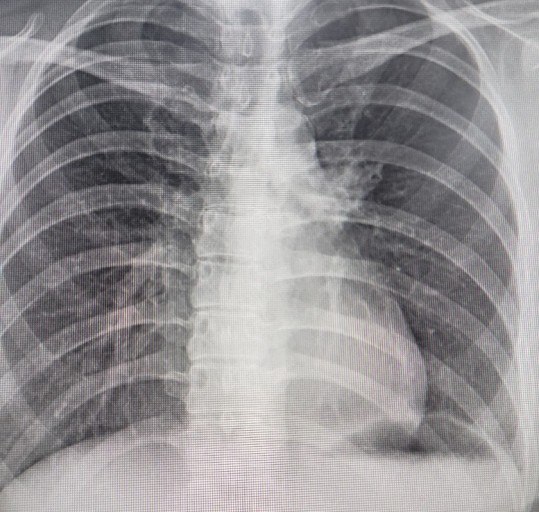

폐렴 치료방법

폐렴의 치료 방법은 원인에 따라 다르지만, 일반적으로 다음과 같은 치료가 진행됩니다:

폐렴은 조기에 치료하면 완치가 가능하지만, 늦으면 합병증이 발생할 수 있으므로 증상이 나타나면 즉시 의료기관을 방문하는 것이 중요합니다.